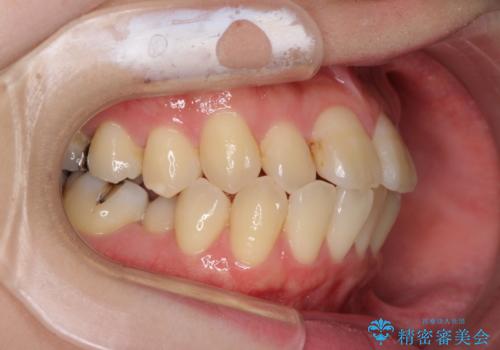

- 下顎の歯が舌側に倒れていることと、前歯の咬み合わせの不具合を気にして来院された患者様です。

受け口傾向の口元であるため、下顎左右小臼歯各1歯を抜歯して歯列を整えることとしました。